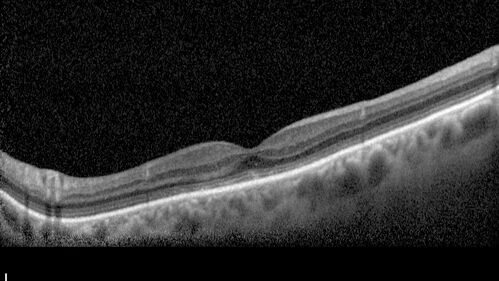

Mild Cone Dystrophy - CRX Mutation

65 year old female with minimal symptoms and a mild cone dystrophy.